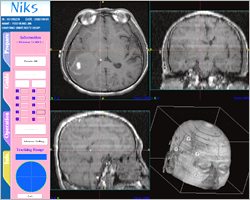

지난 11월 본교 '차세대 지능형 수술 시스템개발 센터'에서 '의료영상을 이용한 기능분석 치료계획 및 수술유도 시스템'을 개발, 발표한 것으로 뒤늦게 알려졌다. 의대 신경외과 김영수 교수를 중심으로 박종일(공대·전컴) 교수, 이병주(공학대·전컴) 교수와 정완균(포항공대·기계공학) 교수로 구성된 '차세대 지능형 수술 시스템개발 센터'가 2002 보건의료기술진흥사업의 일환으로 개발한 수술용 네비게이터 'Niks'는 3차원의 수술영상을 제공하며 정확한 지표인식을 가능케 해, 신경외과 수술의 수준을 한 차원 높일 수 있을 것으로 기대되는 신기술이다.

센터는 이러한 목표를 완성하기 위해 임상에 유용한 지능형 수술 네비게이션 시스템의 개발, 수술 부위의 변화를 실시간으로 반영하는 고화질, 고정밀 증강현실(Augmented Reality) 기술 개발에 주력하고 있다. 또한 실제 임상 적용이 가능한 인간보조수술로봇(Human assistive surgery robot) 및 인간 유도 수술로봇(Human Guided Surgery Robot) 용 햅틱장치(일반적으로 촉각과 힘에 대한 감각을 통합하여 제시할 수 있는 장치) 기술을 개발하여, 최종적으로 이러한 기술들을 통합한 지능형 수술 시스템을 완성하려는 목표를 가지고 있다.